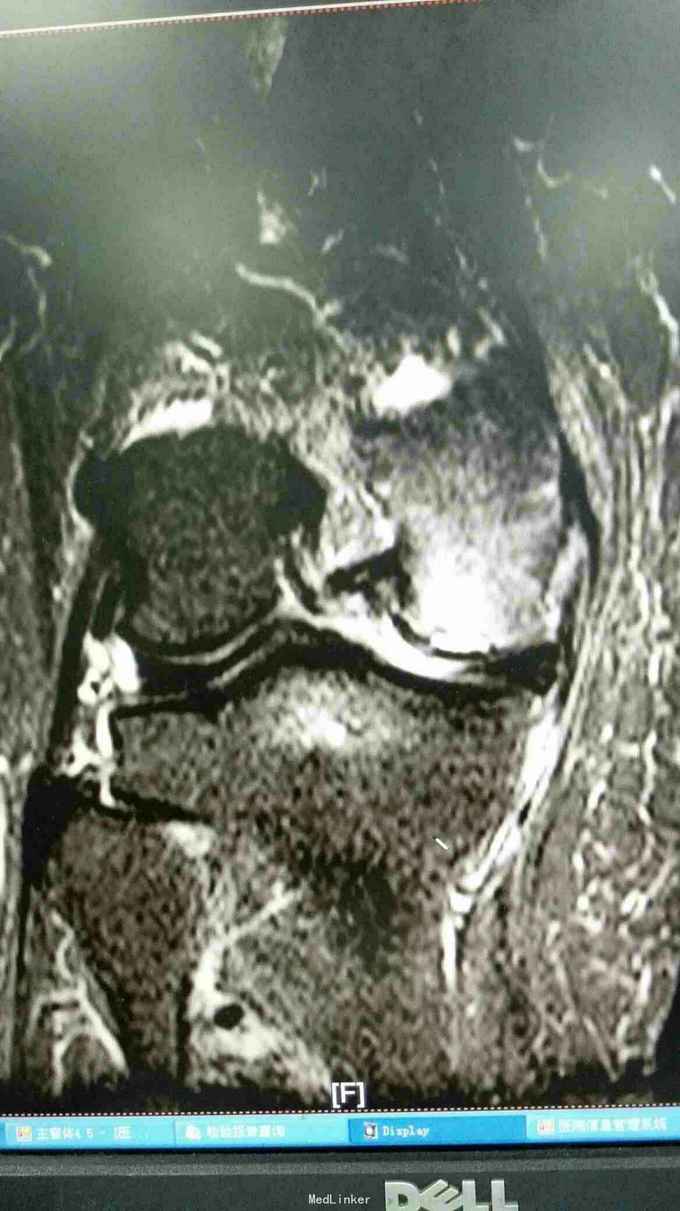

右膝外形正常,皮温正常,右膝内前方压痛(+),前后抽屉试验(-),侧方应力试验(-)、研磨试验内侧(+),关节活动度正常,左膝正常。 站立位膝关节正侧位片提示:右膝关节轻度退行性变,内侧关节间隙稍变窄 右膝关节MRI提示:右股骨内侧髁水肿,考虑局部骨坏死 实验室检查:各炎症指标均正常

诊断:1、右股骨内侧髁骨坏死 2、右膝关节骨性关节炎 治疗:行右膝关节单髁置换术